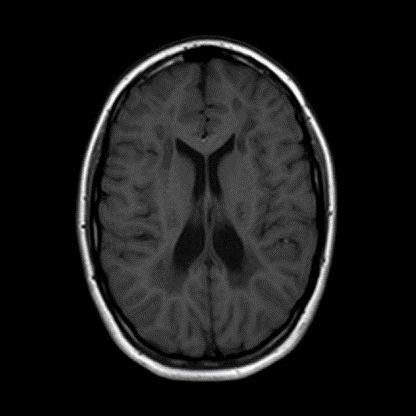

- B) Kontrastsız T1A serilerde tarifli alanlarda hipointens (oklar) görünüm izlendi. Kontrastlı T1A serilerde bu düzeyde (oklar) kontrastlanma artışı izlenmedi. Diffüzyon ağırlıklı serilerde belirgin diffüzyon kısıtlaması (oklar) görülmedi.

- Etkilenen bölgelerde T1’de hipointens, T2/FLAIR’da hiperintens sinyal değişiklikleri izlenir. DWI’de lezyonların periferinde kısıtlı difüzyon görülebilir. MRS’de beyaz cevherde laktat artışı saptanabilir, ancak bu her hastada mevcut değildir.